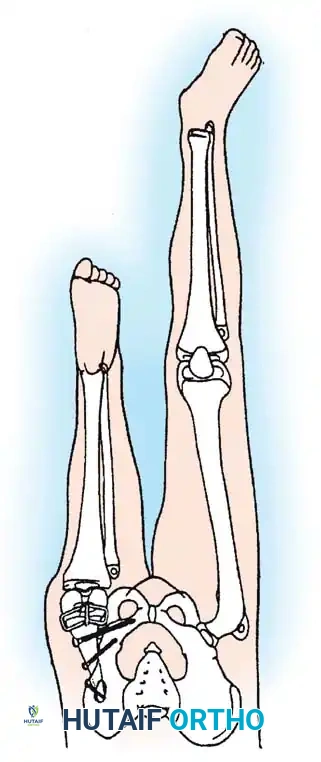

Historically, Brown described a reconstruction for Type 1A tibial hemimelia in which the fibula was surgically centralized and transferred into the intercondylar notch of the femur to create a neo-tibia.

The treatment of choice is a proximal tibiofibular synostosis combined with a Syme amputation or complex distal reconstruction. Creating a synostosis between the fibula and the proximal tibia creates a uniform, in-line, weight-bearing mechanical axis. If the fibula is not surgically transferred and fused to the tibia, a peculiar, curved, hypertrophied fibula develops, causing a severe secondary deformity. Fusing the fibula underneath the tibia encourages its hypertrophy in a mechanically advantageous alignment.

For Type 1B and Type 2 tibial hemimelia, centralizing the mechanical axis is critical. The fibula must be brought under the mechanical axis of the femur or the existing proximal tibial anlage.

Technique Overview:

1. A lateral or anterolateral approach is utilized to expose the proximal fibula and the tibial anlage.

2. The proximal fibula is carefully osteotomized or mobilized, taking extreme care to protect the common peroneal nerve, which often has an anomalous course in these patients.

3. The cartilaginous tibial anlage is split or prepared to receive the proximal fibula.

4. The fibula is centralized beneath the tibia/anlage and fixed using smooth Kirschner wires or a small fragment plate, depending on the child's age and bone quality.

5. Bone graft (autograft or allograft) is packed around the synostosis site to promote rapid union.

By fusing the fibula to the tibia, the surgeon prevents the progressive lateral bowing and hypertrophy of the fibula that inevitably occurs if it is left in its native, eccentric position. This synostosis provides a robust, centralized bony column that can later be lengthened or fitted with a prosthesis following a distal Syme amputation.